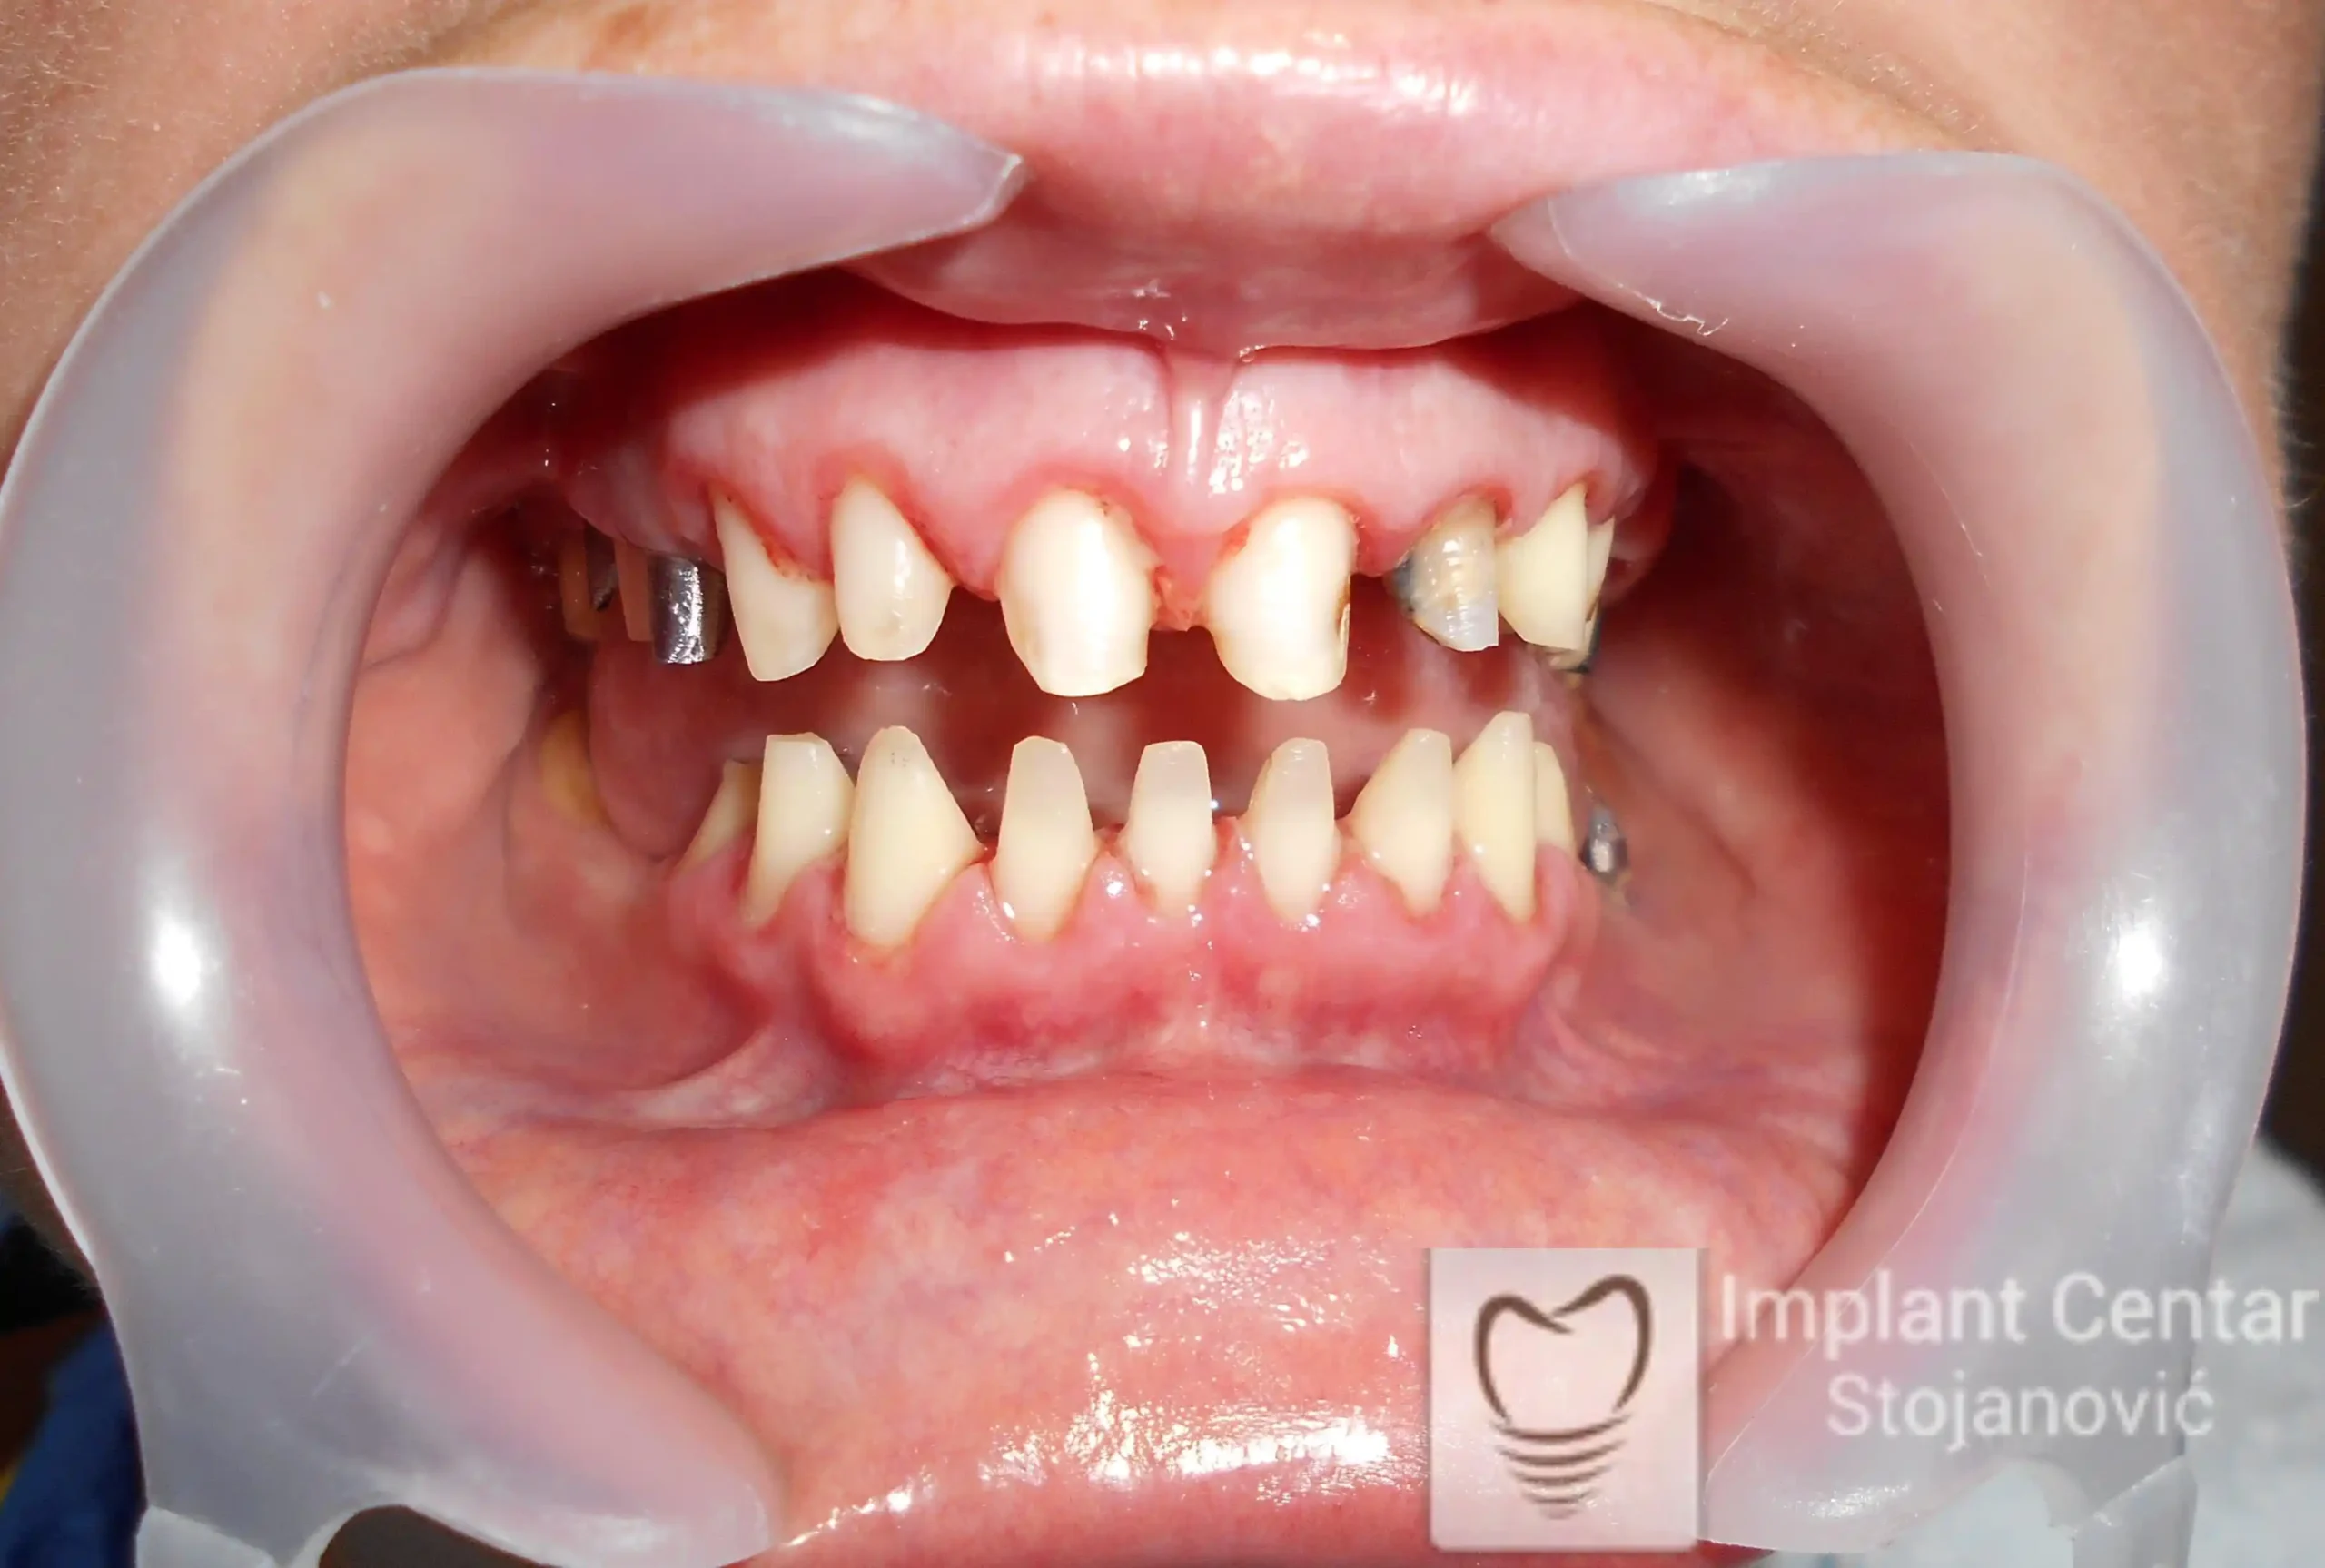

Na slikama 1, 2, 3 , 4  i  5 prikazan je izgled pacijenta pre početka terapije. Nakon detaljne kliničke i radiološke analize, doneta je odluka o vađenju zuba loše biološke vrednosti, dok su bezuba polja sanirana ugradnjom dentalnih implantata.

Nakon ugradnje implantata i pripreme preostalih zuba, pacijentu su izrađene fiksne privremene krunice, čime je postignut eugnatan zagriz već nakon jednog dana (slika 8, 9 i 10). Tokom perioda osteointegracije, pacijent se postepeno privikavao na novi položaj vilica i zagriz.

Po završetku perioda integracije, izrađeni su definitivni cirkonijum-keramički mostovi, čime je postignuta potpuna rekonstrukcija zagriza, kao i značajno poboljšanje estetike i oralne funkcije (slika 12, 13, 14 i 15).